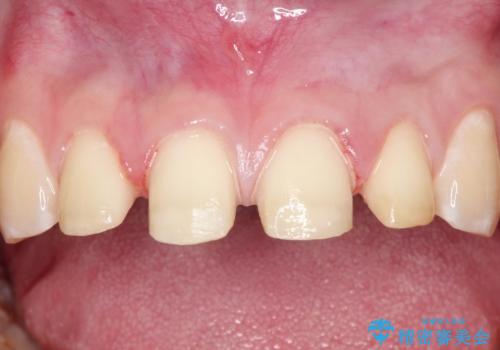

- 前歯をきれいにしたいとのご希望がありました。

生まれつき歯の色が白濁しているところや、黄色くなっているところがあり、セラミッククラウンに審美的改善を行うこととしました。